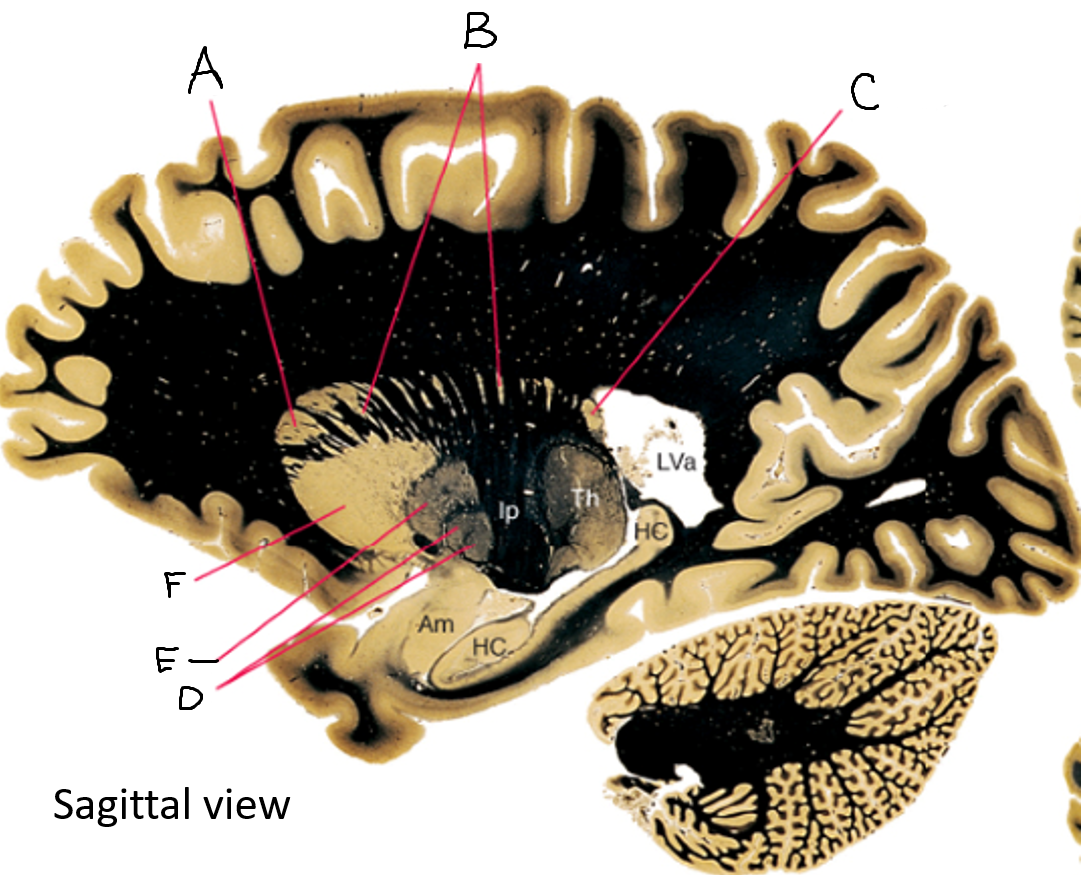

B

anterior horn of lateral ventricle

C

head of caudate nucleus

D

internal capsule (anterior limb)

E

putamen

F

globus pallidus

G

Thalamus

H

External capsule

I

internal capsule (posterior limb)

J

tail of caudate nucleus